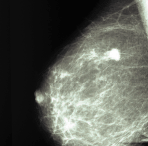

Mammografi

Sundhedsstyrelsen anbefaler kvinder, hvis menstruationer er ophørt at få undersøgt deres bryst med mammografi hvert andet år. Kvinder der har implantater, bliver ofte tilbudt ultralydscanning i stedet for mammografi, så der ikke er risiko for at implantatet "skjuler" en kræftknude.

Mammografi anbefales hvert andet år til patienter over 50 år.